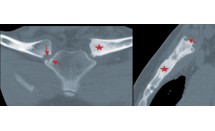

Spondylarthropathie/Spondylarthrite ankylosante